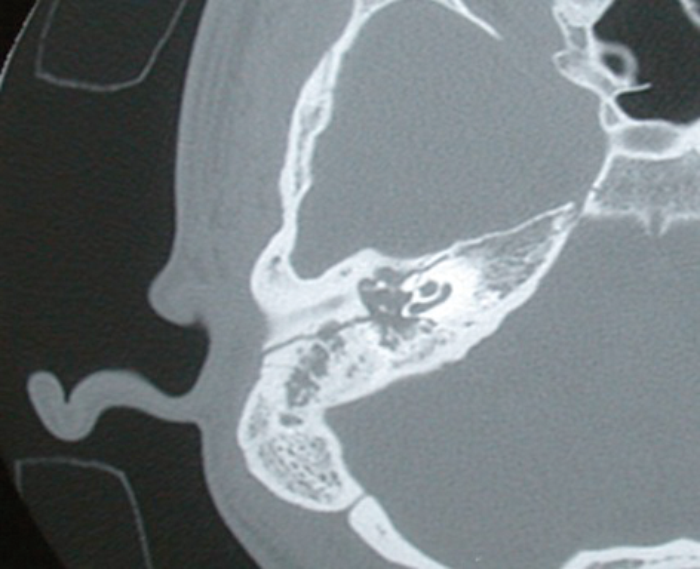

Temporal bone trauma

Introduction Temporal bone injuries represent one of the more complex management problems presenting to the otolaryngologist. This is largely due to difficulties in assessment and the frequent delays in referral, often as a result of other injuries demanding more immediate...